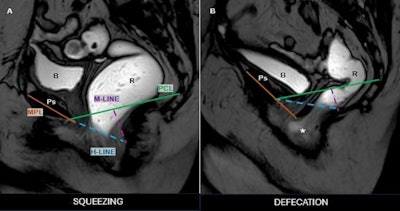

Anterior rectocele with pelvic floor descent during defecation phase, consistent with pelvic floor dyssynergia and structural pelvic organ prolapse. Midsagittal fast field echo (BFFE) images during the squeezing phase (left) and defecation phase (right) demonstrate anorectal angle dynamics. During defecation, note the presence of an anterior rectocele (*), protruding beyond the H-line, indicating pelvic floor dysfunction. Pubic symphysis (Ps), rectum (R), bladder (B).Pugliesi et al; EJR